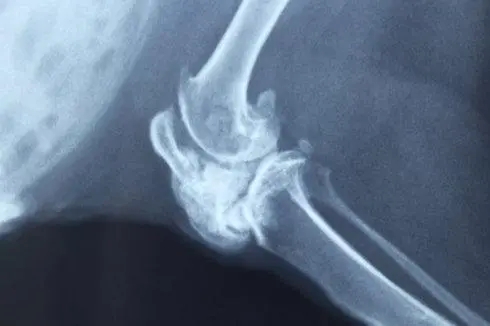

X線所見影像典型,可在組織學(xué)診斷之前作出診斷。

基本影像是密度增高不透X線的影像,是由于腫瘤內(nèi)軟骨的鈣化、骨化所引起。與中心性軟骨肉瘤相比,周圍性軟骨肉瘤的鈣化更常見且更廣泛,在許多病例中,這種密度增高的影像幾乎遍布整個(gè)腫物。因此,在周圍性軟骨肉瘤中,可看到一骨外腫物,呈模糊分葉狀,表面凹凸不平像花椰菜樣,密度很高。在腫瘤較厚的區(qū)域不引起象牙狀的高密度影像,可以看到鈣化無一定的結(jié)構(gòu),呈典型的結(jié)節(jié)狀、點(diǎn)狀和環(huán)形(相應(yīng)于軟骨樣的分葉和周邊形成)。腫物表面的鈣化較少,至使腫瘤與軟組織的界限模糊。

在很少見的極早期病例中,周圍性軟骨肉瘤在影像上仍表現(xiàn)為骨軟骨瘤的影像,其惡性演變可通過CT、MRI、大體病理和組織病理而確定,其骨掃描不是在成人期應(yīng)當(dāng)?shù)年幮?,而是?qiáng)陽性。